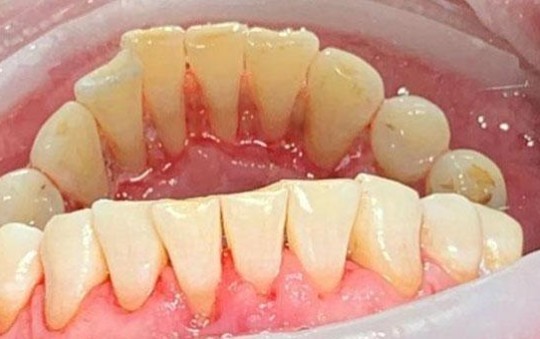

На странице представлено портфолио стоматологий Москвы с работами до и после профессиональной чистки зубов. В нашем портфолио собраны разные клинические случаи: от удаления незначительного налета до снятия массивного поддесневого камня. Здесь вы можете увидеть, как возвращается естественный цвет и внешний вид зубов после процедуры. Изучите результаты до и после чистки зубов, чтобы увидеть реальный эффект и выбрать клинику в Москве, где профессиональная гигиена поможет вернуть зубам здоровый вид.

Чистка зубов Air-flow